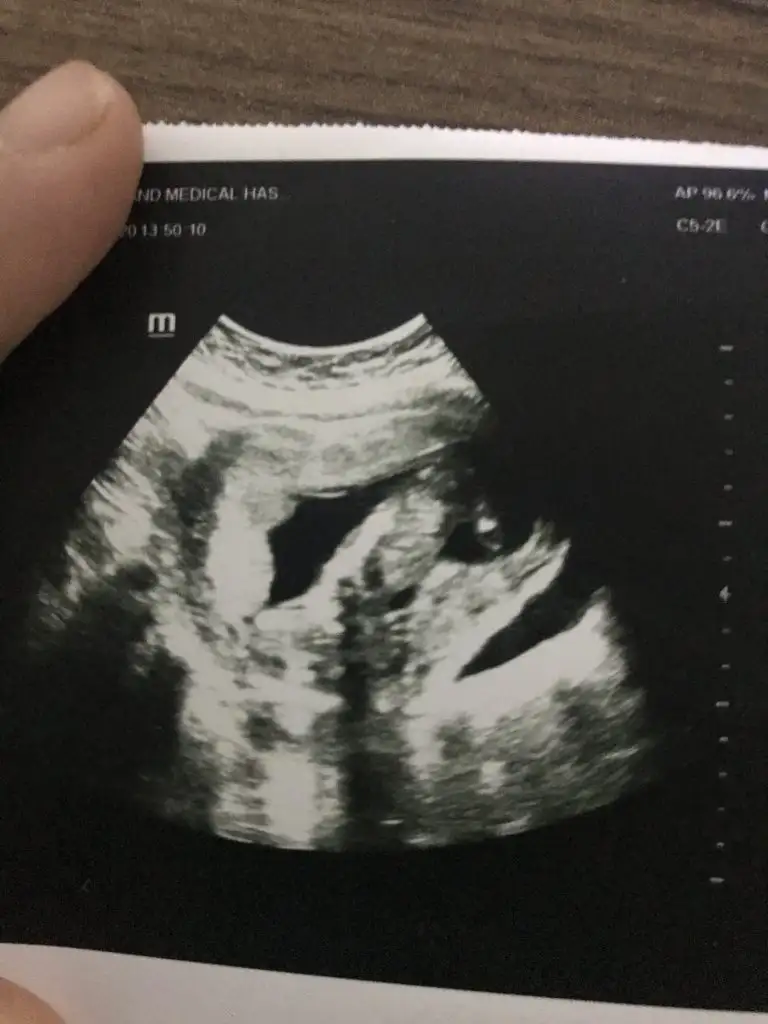

dün gittik 14 hafta usg verdi ama belli olmuyor

Buda kız gibi boş görünüyor bacak arasıdün gittik 14 hafta usg verdi ama belli olmuyor Eki Görüntüle 2575104